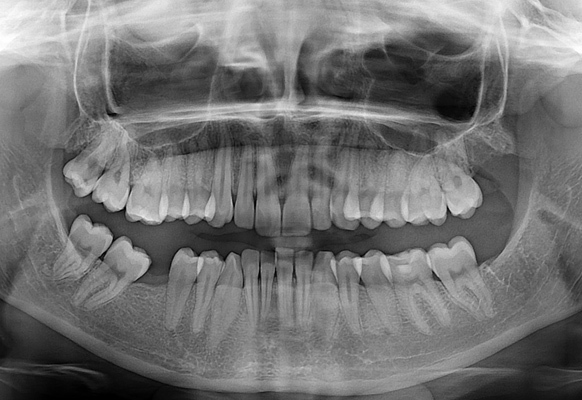

Zdrowy uśmiech zaczyna się od dokładnej diagnozy. Zdjęcia RTG pantomograficzne pozwalają na kompleksową ocenę stanu uzębienia, a także kości szczęki i żuchwy. W ESDENT wykonujemy je szybko, bezboleśnie i z maksymalną dokładnością. Przy dawce promieniowania tak małej, jak to tylko możliwe.

Jedną z naszych specjalizacji w placówce ESDENT w Poznaniu jest wykonywanie szczegółowych zdjęć pantomograficznych RTG, wykorzystywanych w procesie analizy stanu uzębienia, kości szczęki i żuchwy w celach przedzabiegowych i kontrolnych. Pracujemy na bezpiecznych aparatach, stawiając na pierwszym miejscu zawsze dobro pacjenta.

Zdjęcie pantomograficzne jest kluczowym narzędziem diagnostycznym w stomatologii ogólnej i jako wstępna diagnoza w innych specjalizacjach. Wykonuje się je w celu: